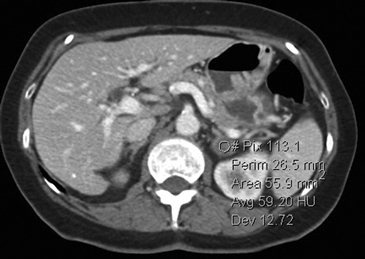

La presencia de lípidos intracelulares disminuye la densidad de la lesión debido a que estos son menos densos que el agua. El primer estudio en reportar la utilidad de la densitometría por TC en la diferenciación de una lesión suprarrenal benigna de una maligna fue el realizado por Lee et al6, utilizando la medición del coeficiente de atenuación o densidad de la lesión expresada en unidades Hounsfield (UH), en una TC no contrastada, demostrando que el coeficiente de atenuación promedio de los adenomas (2,2 UH) fue significativamente menor que la de las lesiones no adenomas (28,9 UH). Utilizando un punto de corte de 0 UH la sensibilidad de la TC no contrastada en la caracterización de un adenoma es cercana a un 47%, con una especificidad de aproximadamente 100% (Figura 9 a y b). Sin embargo, estudios posteriores7 han corroborado que al utilizar un punto de corte de 10 UH, la sensibilidad asciende a un 71%, y la especificidad se mantiene en prácticamente 98%, por lo que este umbral de densidad es el más utilizado en la actualidad. Es importante enfatizar que para una adecuada medición de la densidad, la región de interés (ROI) no debe incluir áreas de necrosis ni de hemorragia, y debe abarcar al menos la mitad o dos tercios de la lesión, para evitar el artefacto por ruido y el efecto de volumen parcial con el tejido adiposo adyacente (Figura 10).

Figura 10. Adenoma suprarrenal derecho. Lesión suprarrenal derecha, cuya densidad es consistente con un adenoma típico. En la imagen se demuestra una adecuada medición de la densidad lesional, con una región de interés (ROI) que abarca al menos dos tercios de ésta.

Los valores más utilizados son un 40% de lavado relativo de en fase tardía realizada a los 15 minutos y un lavado absoluto de 60%. De este modo cualquier lesión que muestre un lavado relativo mayor al 40% o absoluto mayor al 60% es consistente con un adenoma, con una sensibilidad y especificidad cercana al 100% (Figura 14 a, b y c). Dado la rapidez con que se obtiene un TAC de abdomen en la actualidad, algunos trabajos han recomendado utilizar cortes tardíos realizados a los 10 minutos, con el fin de optimizar el tiempo de examen, y utilizar un valor relativo de corte más conservador del 50%9.

C Figura 14. Tomografía computada de un adenoma suprarrenal izquierdo típico. Se ha colocado un circulo que representa la región de interés en la lesión de la glándula suprarrenal izquierda, obteniendo una medición promedio (Avg) expresada en unidades Hounsfield (UH). En fase precontraste (a) su densidad es de 0 UH, (flecha), en fase protovenosa (b) alcanza una densidad de 59 UH (cabeza de flecha), y en fase tardía (c) su lavado es de aproximadamente un 50%, llegando a una densidad de 30 UH.